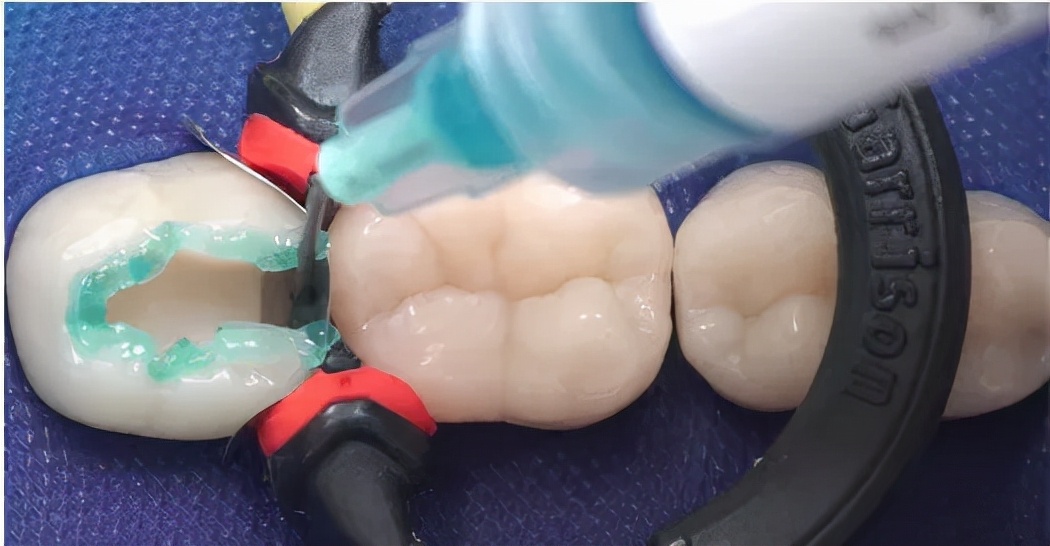

复合树脂, 接近牙齿颜色的填充材料,粘接性还不错,特别耐磨抗腐蚀,关键补牙后还看不出有补过痕迹,大人和小朋友都可以使用。

应对方式: 根管治疗+补牙,前牙根管+普通树脂,后牙根管+进口树脂